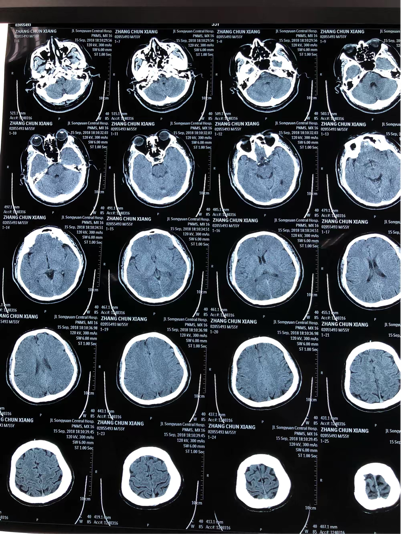

2、脑部CT平扫没有什么副作用,一次脑部CT平扫的辐射剂量是2msv,辐射剂量很低且对人体没有副作用如果患者做的是脑部CT增强检查或者脑部血管检查,这种情况需要注射造影剂,检查前需要详细询问患者的病史及其过敏史如果是严重的甲亢或者对碘造影剂过敏,不可以做脑部增强CT检查或者脑部血管检查因为造影剂有;有脑CT检查是一种常见的医学检查方式,通过该检查可以检测大脑是否存在疾病或损伤通常,脑CT检查对大脑没有损害但在进行脑CT检查时,有时会出现一些不适或不良反应,例如头痛恶心呕吐和眩晕等这些反应通常是短暂的,并且通常不需要特殊治疗;1 辐射暴露脑部CT需要使用X射线,因此会暴露人体于辐射中尽管CT射线剂量相对较低,但长期或高剂量的暴露可能增加患病的风险,例如白血病和其他癌症2 对孕妇和胎儿的影响孕妇进行脑部CT扫描时,射线暴露可能对胎儿造成潜在的危害特别是在妊娠早期,射线可能对胎儿的发育有负面影响,因此孕妇应在。

3、脑部CT平扫无副作用一次脑部CT平扫的辐射剂量非常低,对人体没有副作用脑部CT增强检查或脑部血管检查造影剂使用这类检查需要注射造影剂,因此检查前需详细询问患者的病史和过敏史甲亢及过敏患者禁忌对于严重甲亢或对碘造影剂过敏的患者,不可以进行脑部增强CT检查或脑部血管检查,因为造影剂可能;建议合理使用尽管脑CT的损害较小,但仍建议在医生的指导下合理使用,避免不必要的检查,以减少潜在的放射线暴露综上所述,脑CT对大脑有一定的损害,但这种损害在大多数情况下被认为是非常小的,并且在紧急情况下,其诊断价值远远超过了潜在的损害因此,在医生的建议下进行脑CT检查是安全的;脑CT的副作用主要指放射线对人体的放射损伤,但单次脑部CT通常不会对人体有明显影响以下是具体的解释放射损伤频繁的脑CT检查可能会使人体受到大量的射线损伤这些损伤可能包括白细胞的下降生殖细胞损伤以及各脏器肿瘤发生率增加等情况技术进步与辐射量降低随着脑CT技术的不断进步,仪器性能越来;脑部CT检查的危害主要包括以下方面1 辐射危害脑部CT通过X射线断层扫描成像,单次检查的辐射剂量虽在安全范围内,但长期或多次检查可能累积辐射暴露,增加患癌风险,尤其是对儿童青少年及辐射敏感人群世界卫生组织指出,辐射剂量与癌症风险呈正相关,需严格控制检查频率2 过敏反应增强CT需注射碘基造;CT主要是依靠发射X射线,对人体组织进行投射而发现病变,X射线对身体细胞肯定是有杀伤作用的,如果X射线照射的时间过长或者剂量过大,就可能会导致人体的细胞发生癌变如果是孕妇,可能会出现胎儿畸形,所以,怀孕前3个月是避免查CT的要从X射线对人体致癌的角度来讲,通常需要有一定量的X射线,做一次;2要放松心态为好,这种ct检查的辐射都是安全范围以内的,不要过于担心,否则过于紧张倒是会导致身体的不适症状发生的,任何事情还是往简单里考虑为好3可以采取预防辐射的损害措施,可以通过检查后食用海带,绿豆汤,绿茶等促进射线排出,减少辐射损伤看来脑部ct有辐射是一定的,但是对人体造成大的。

4、2 静脉造影剂的风险在某些情况下,医生可能会给患者注射一种叫做静脉造影剂的药物,以增加扫描图像的清晰度然而,静脉造影剂有潜在的风险,如过敏反应肾功能受损等3 误诊的风险有时,脑部CT图像可能被解读错误,导致误诊或漏诊这可能会延误正确的治疗,导致患者的健康问题进一步恶化总的;婴儿偶尔进行脑部CT检查通常不会造成明显伤害,但频繁检查可能带来以下危害1 辐射对细胞的直接损伤CT检查依赖X射线辐射成像,当辐射穿透人体时,会破坏组织细胞内的DNA结构婴儿细胞分裂活跃,对辐射的敏感性远高于成人,尤其是脑部神经细胞偶尔一次检查的辐射剂量在安全范围内通常低于5mSv,但多次;脑部CT检查本身在规范操作下危害极小,但存在特定风险及禁忌需注意其安全性与检查必要性个体情况及操作规范密切相关,具体分析如下一潜在风险与副作用脑部CT通过X射线成像,单次检查的辐射剂量通常在安全范围内成人头部CT约2mSv,远低于年辐射限值50mSv,但多次检查可能增加辐射累积风险,需避免;脑部CT计算机断层扫描是一种医学影像检查技术,用于观察和诊断脑部疾病和损伤一般情况下,脑部CT检查是安全的,但仍存在一些潜在的危害和副作用1 射线暴露脑部CT检查使用X射线,因此暴露于辐射尽管剂量较低,但频繁的CT扫描或长期暴露可能增加癌症风险2 对孕妇和胎儿的影响孕妇接受脑部CT。

5、做脑部的CT是没有任何的危害的,脑部CT属于放射线的检查,1次检查的时间是非常短暂的,在1分钟左右就已经完成检查,而且1次放射线的量是非常小不会对身体造成任何的影响,但是需要注意的是做脑部CT如果是儿童就需要进行防护,患者脖子上要进行防护,因为一定的放射线会对儿童的甲状腺有一定的破坏,而成年;做脑部CT检查可能带来的副作用如下1放射性暴露脑部CT检查依赖X射线扫描,患者会接受一定剂量的电离辐射尽管单次检查的辐射量通常处于安全范围,但长期或频繁接受CT检查可能增加辐射累积风险孕妇儿童及免疫力低下人群需特别谨慎,因辐射可能对胎儿发育或儿童组织造成潜在影响医生会在检查前评估个体风。